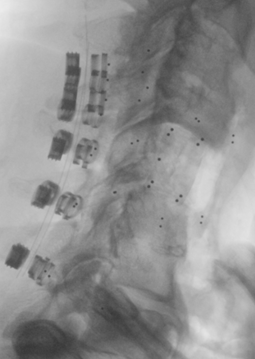

The first stage was a posterior approach with a C3-T3 instrumented fusion using CMORE® Carbon/PEEK lateral mass and pedicle screws (Fig 2) with resection of the posterior elements of C6, mobilization of the C6 and C7 nerve roots and vertebral arteries bilaterally. The second stage was a left sided anterior cervical approach with completion of the C6 spondylectomy and en bloc resection of the C6 lesion. The resected lesion tissue is shown in Fig 3.